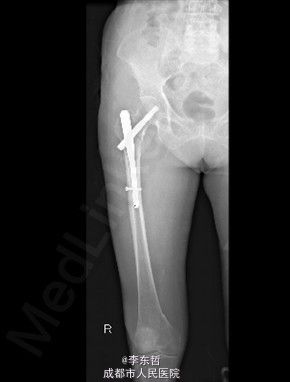

查体:T:37.2oC,P:72次/分,R:18次/分,BP:124/68mmHg。神志清楚,急性病容,皮肤巩膜无黄染,全身浅表淋巴结未见肿大。。颈静脉正常。心界正常,心律齐,各瓣膜区未闻及杂音。胸廓未见异常,双肺叩诊呈清音,双肺呼吸音清,未闻及干湿啰音及胸膜摩擦音。腹部外形正常,全腹柔软,无压痛及反跳痛,腹部未触及包块,肝脏肋下未触及,脾脏肋下未触及,双肾未触及。双下肢无水肿。 专科查体见:右髋关节局部肿胀,周围无红肿、皮肤损伤、溃疡和糜烂,右下肢短缩畸形,无表浅静脉曲张。右转子间轻触痛,扣痛。右髋活动受限,右下肢短缩畸形约5cm,轻度外旋、内收。右髋关节屈伸、外旋内旋、外展内收功能障碍。 X线片示:右股骨转子间骨折,累及大小转子,断端稍分离,未见明显错位,周围软组织肿胀明显,右髋关节在位。

初步诊断:1、右股骨转子间骨折(Evans III型);2、骨质疏松症。 诊疗计划:1、向患者及家属交待病情及注意事项。2、向上级医生汇报患者病情。3、完善术前相关检查。4、给予皮肤牵引、抬高患肢等对症处理。5、拟手术治疗。6、密切观察病情变化,根据病情及时处理。